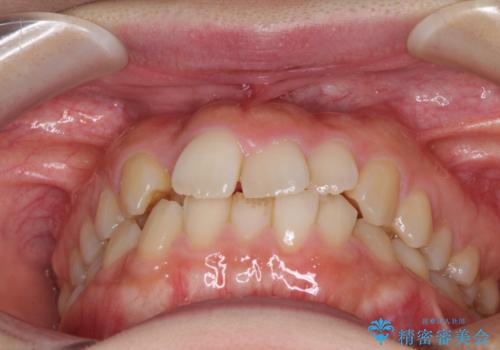

- 右上の八重歯と、左下八重歯を抜いてしまったことを気にして来院された患者様です。

下顎は既に犬歯を1本抜歯しているため、上顎右側第一小臼歯を抜歯し、ワイヤー装置にて歯列を整えることとしました。

変則的な抜歯となるため、正中と人中がずれる可能性がありましたが、仕上がりは上下正中を揃えることができました。